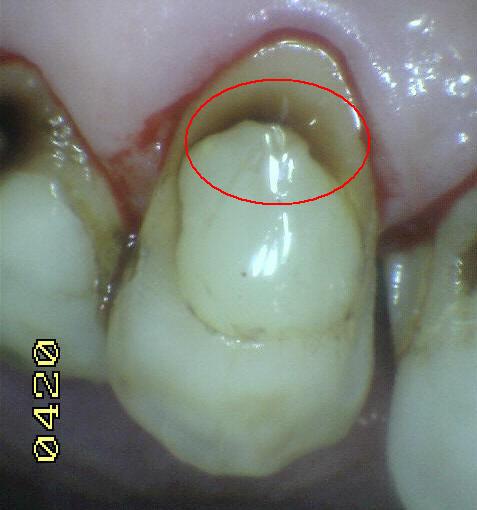

Código 4

(Caries Moderada): Sombra oscura

de dentina subyacente al esmalte intacto con o sin interrupción

localizada del esmalte

- La superficie de los dientes

puede tener características de código 2 y tiene una

sombra de dentina con cambio de color que es visible a

través de una superficie de esmalte aparentemente

intacto o con ruptura localizada en el esmalte pero sin

dentina visible. Este aspecto se ve más fácilmente

cuando el diente está húmedo y es una sombra oscura e

intrínseca que puede ser de color gris, azul, naranja o

café.

- Nota: observar el diente húmedo y luego seco. Esta

lesión debe distinguirse de sombras ocasionadas por

amalgama.